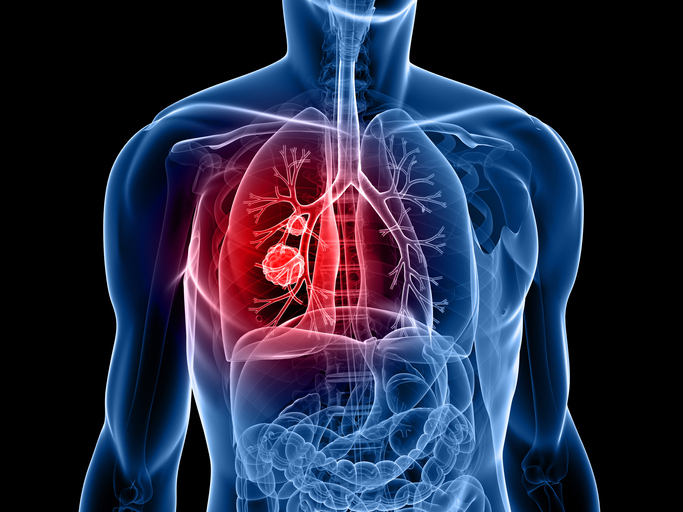

폐렴 증상 3. 호흡 곤란 및 숨 가쁨

폐에 염증이 생기면 산소 교환이 어려워져

숨이 차고 가슴이 조이는 느낌,

또는 평소보다 가쁜 숨, 짧은 호흡이 나타날 수 있어요.

계단을 오르거나 평소보다 조금만 움직여도 숨이 찰 수 있습니다.4. 흉통(가슴 통증)

기침하거나 숨을 깊게 쉴 때 가슴, 특히 흉부에 찌르는 듯한 통증이 발생할 수 있습니다.

이는 염증이 **늑막(폐를 감싸는 조직)**까지 퍼졌기 때문이에요.